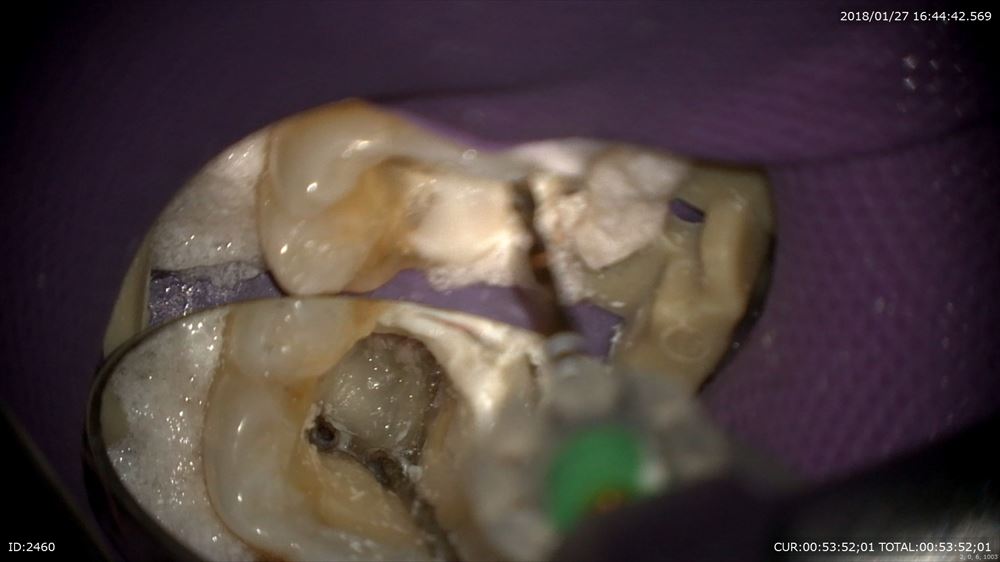

被せ物を外して、ラバーダム。これがないと失敗します。

このようにマイクロスコープで感染を丁寧に除去。突然膿が温泉のように。。。。